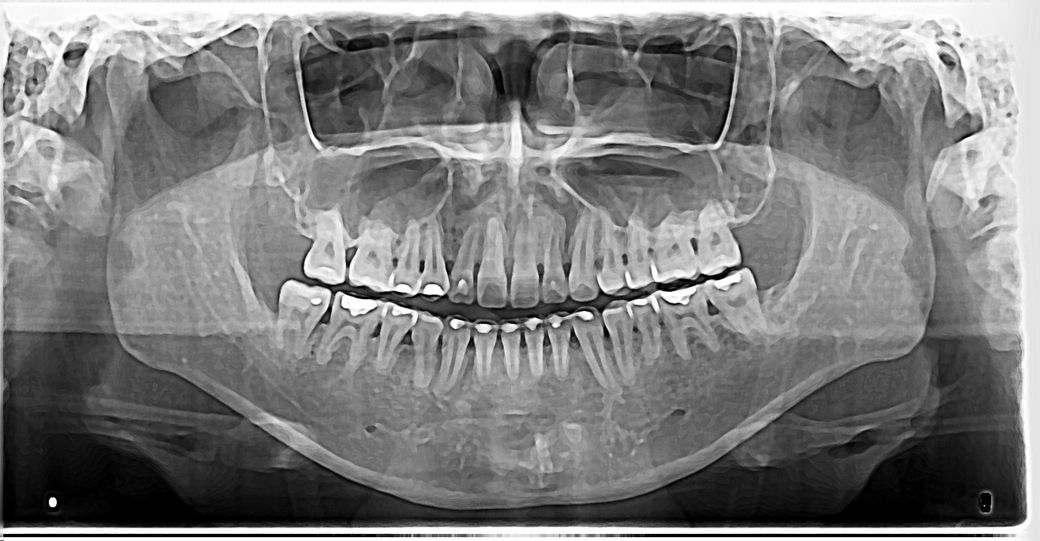

안녕하세요. 1번째 사진은 20살 첫교정 전에 장치만 달은 엑스레이구요. 오른쪽 윗 송곳니 어릴때 빼서, 저때도 비대칭으로 살짝 턱이 왼쪽으로 틀어져있었어요.

• 1번 째 사진